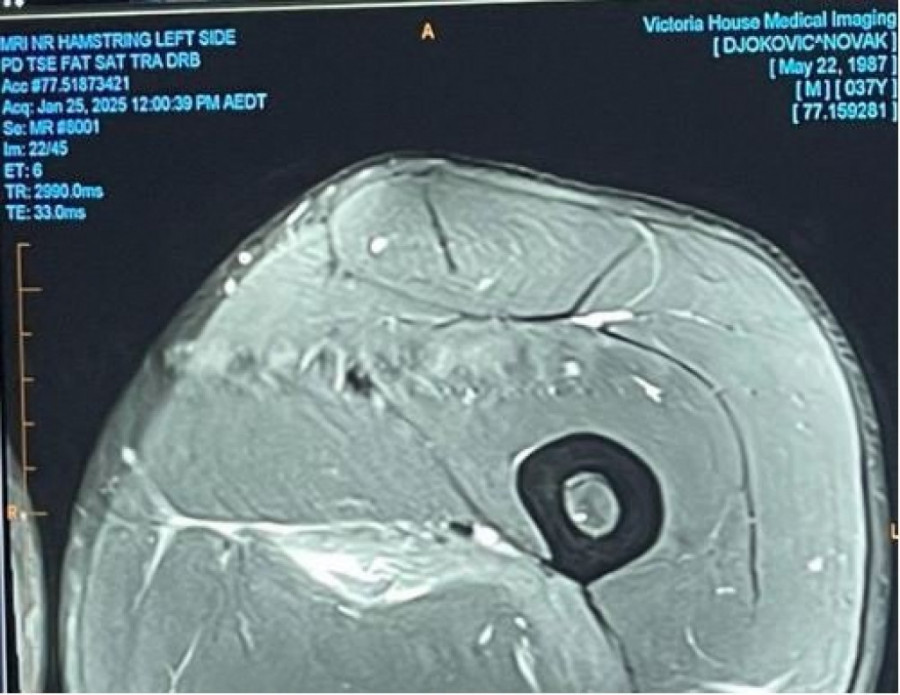

U nastojanju da pruži jasnoću i transparentnost, Đoković je javno podelio rendgenski snimak oštećenja tetive, osvetljavajući ozbiljnost situacije. Slika je poslužila kao vizuelna potvrda izazova s kojima se suočava u procesu oporavka, a neke prve informacije su govorile da će Đoković oko dva meseca pauzirati.